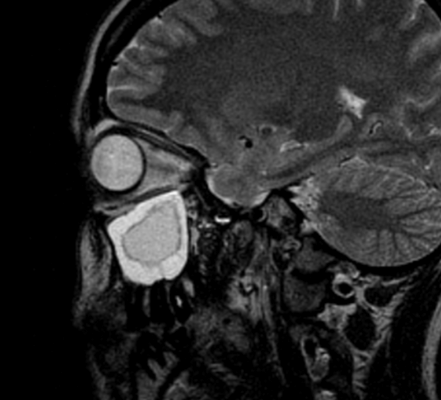

Слева — КТ-снимок одонтогенной кисты в верхнечелюстном синусе, справа — МР-фото образования (указано стрелкой) в гайморовой пазухе